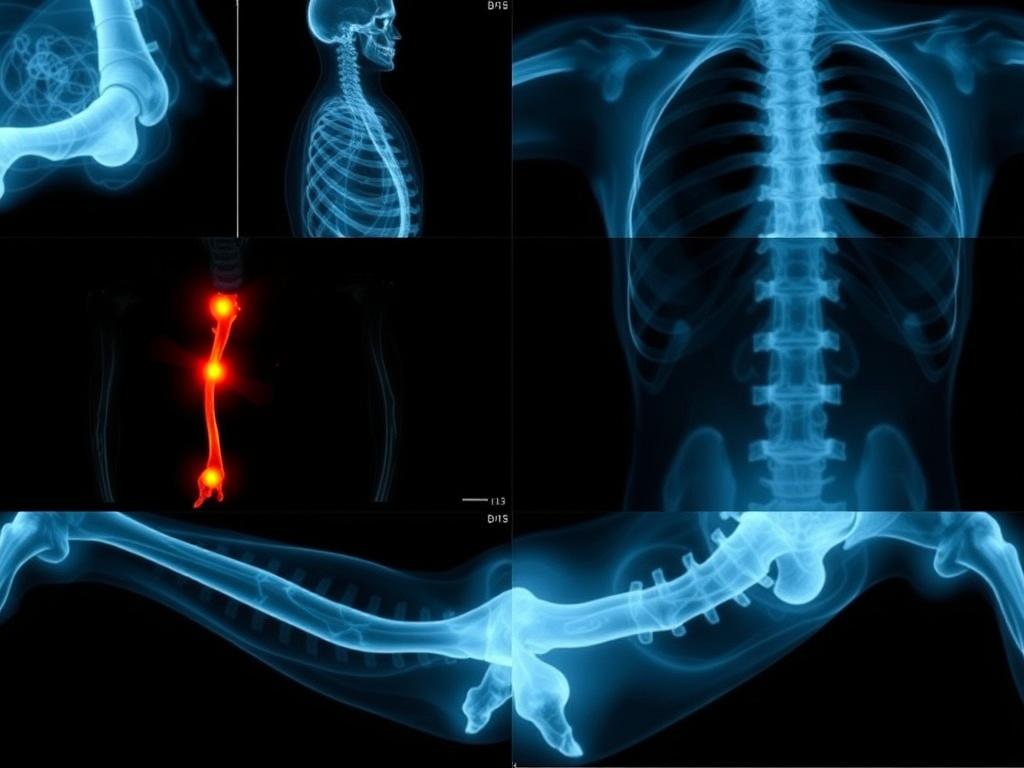

Электронный атлас — это структурированная коллекция радиографических изображений, снабженная подробными аннотациями, маркировкой анатомических ориентиров и классификационными признаками травм. В отличие от печатной книги или одноразового руководства, такой ресурс позволяет интерактивно исследовать каждую серию снимков, сравнивать разные ракурсы и видеть примеры типичных вариантов повреждений. Для врача это значит, что мыслительный процесс становится более систематизированным: от распознавания симптомов до сопоставления с учебной картиной и принятия решения о дальнейшем исследовании или лечении.

Структура атласа обычно предполагает поиск по анатомии, типу травмы, стадии повреждения и возрастной группе пациента. В реальном времени можно переключаться между проекциями, просматривать связанные 3D-модели, а иногда и переходить к сопутствующим методам визуализации, например к компьютерной томографии или МРТ. Это облегчает не только диагностику в условиях стационара, но и обучение: студенты и молодежь быстро получают доступ к большим наборам клинических примеров и наглядным инструкциям.

Основной фокус атласа лежит на костях и суставах всей оси опорно‑двигательного аппарата: от позвоночника до стопы. В разделе позвоночника особое внимание уделяется межпозвонковым дискам, векторам осевых нагрузок и характеру переломов тел позвонков. При травмах конечностей разбираются диафизы, эпифизы и суставные поверхности, а также особенности роста у детей, которые влияют на радиологическую картину. Включены примеры компрессионных переломов, вывихов сустава, дистальных и проксимальных травм, а также сочетанных повреждений.

Важная часть — демонстрация классификаций: где применимы AO/OTA для длинных костей, как распознавать типы вывихов в плечевом суставе, отличать травмы от патологий с похожими радиологическими признаками. Атлас помогает увидеть связь между травмой и клиническим статусом пациента, что особенно важно в условиях ограниченного времени при травмах нагрузок и падений.